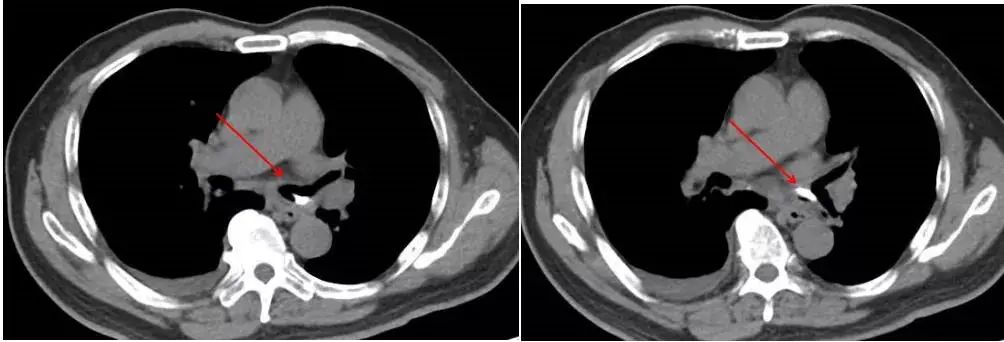

杨叔说:“我知道肺有问题,很可能2年前的鱼骨头在右边,现在开始痛了,可能发炎了”。医生马上给他做了胸部CT。一查除了肺炎、胸水,还有肺栓塞!右边没有发现有异物,反而左边发现闪闪发光的东西。

病情出乎杨叔的想象,不停纳闷着,两年来一直以为异物在右边,现在胸痛也是在右边。赵子文主任医师、张梅春主任医师耐心解释,这次胸痛是肺炎、肺栓塞引起来的,也正因为来医院看病才能发现潜在的风险。而左边支气管的东西,可能真的是两年前误吞的东西。